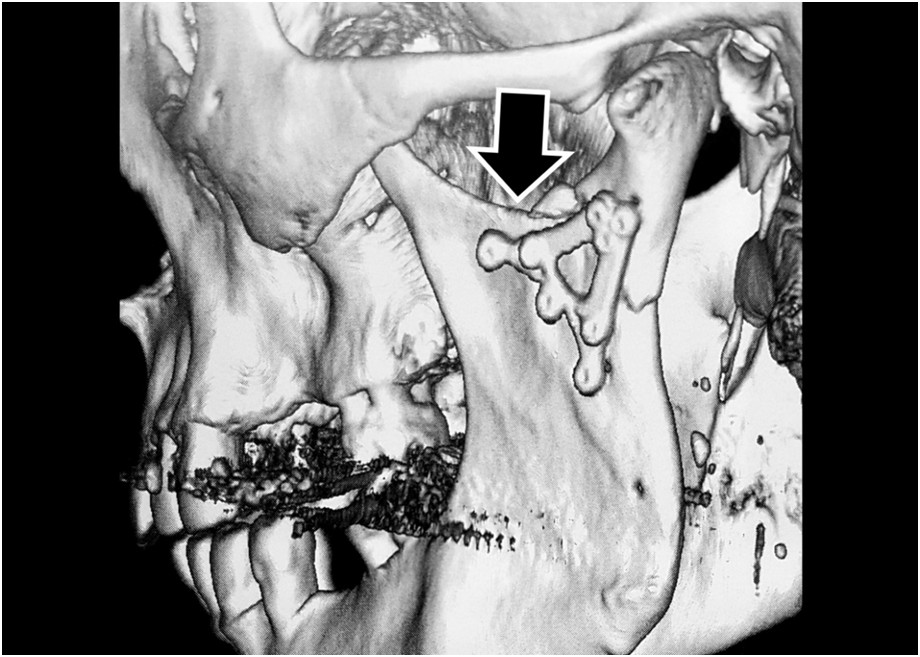

Pytanie 44

Przedstawiono zespolenie niskiego złamania szyjki wyrostka kłykciowego u pacjenta leczonego po urazie. Wskaż prawdziwe stwierdzenie dotyczące zaznaczonego miejsca: